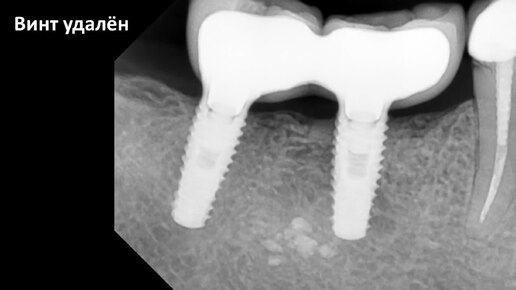

Удаление сломанного винта имплантата типа TL